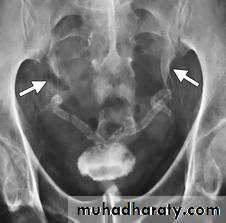

12- Bilateral megaureter

13- Polycystic